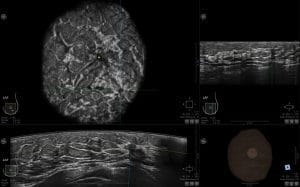

ABUS σε γυναίκα 49 ετών με αρνητική μαστογραφία.

Στο Αυτοματοποιημένο Υπερηχογράφημα ανιχνεύθηκε διαταραχή της αρχιτεκτονικής (με πράσινη ένδειξη)

Η διαδικασία διενεργείται από εξειδικευμένο προσωπικό, τεχνολόγους ή νοσηλευτές, που είναι εκπαιδευμένοι στη συγκεκριμένη τεχνική. Η γυναίκα είναι ξαπλωμένη και το ABUS -το οποίο έχει σχεδόν τριπλάσιο εύρος από τις κεφαλές των συνηθισμένων μηχανημάτων υπερήχων- σαρώνει το μαστό από διαφορετικές γωνίες και μετά ανασυνθέτει την εικόνα και προβάλλοντας σαν σε βίντεο αναλυτικά όλο τον μαστό σε τρισδιάστατη απεικόνιση. Αυτές τις εικόνες λαμβάνουμε μετά στο μόνιτορ και ο ακτινοδιαγνώστης τις διαβάζει. Ουσιαστικά, είναι σαν να βλέπουμε σαν ταινία όλο τον μαστό της γυναίκας. Αυτή η εξέταση μας δίνει μία πιο αντικειμενική εικόνα από αυτή που λαμβάνουμε όταν ένας γιατρός εξετάζει με τον κλασικό υπέρηχο τον μαστό, αφήνοντας ίσως έστω και μικρό ενδεχόμενο να ξεφύγει ένα ελάχιστο σημείο στην περιφέρεια του μαστού και να μείνει υπερηχογραφικά ακάλυπτο. Ταυτόχρονα, το ABUS διαθέτει τεχνολογία τεχνητής νοημοσύνης, που προσθέτει αντικειμενικότητα στην τεχνική. Επειδή, επίσης, δεν υπάρχει, παγκοσμίως, τόσο πολύ προσωπικό εξειδικευμένων ακτινολόγων στους υπερήχους μαστού (καθώς δεν κάνει ο ίδιος ο ιατρός τον υπέρηχο. Στην Αμερική, για παράδειγμα, του υπερήχους τους κάνουν πιστοποιημένοι τεχνολόγοι). Είναι διαφορετικό να διαβάζει ο γιατρός μία δυναμική εξέταση που είναι σαν να βλέπει μπροστά του τον μαστό και είναι τελείως διαφορετικό να μελετάει στατικές εικόνες που θα λάβει από τον τεχνολόγο. Το ABUS υπερτερεί κατά πολύ σε αυτά τα εξαιρετικά σημαντικά σημεία της εξέτασης και της διάγνωσης».

- Η τρισδιάστατη απεικόνιση ογκομετρικών εικόνων (εγκάρσιο, στεφανιαίο, οβελιαίο επίπεδο).